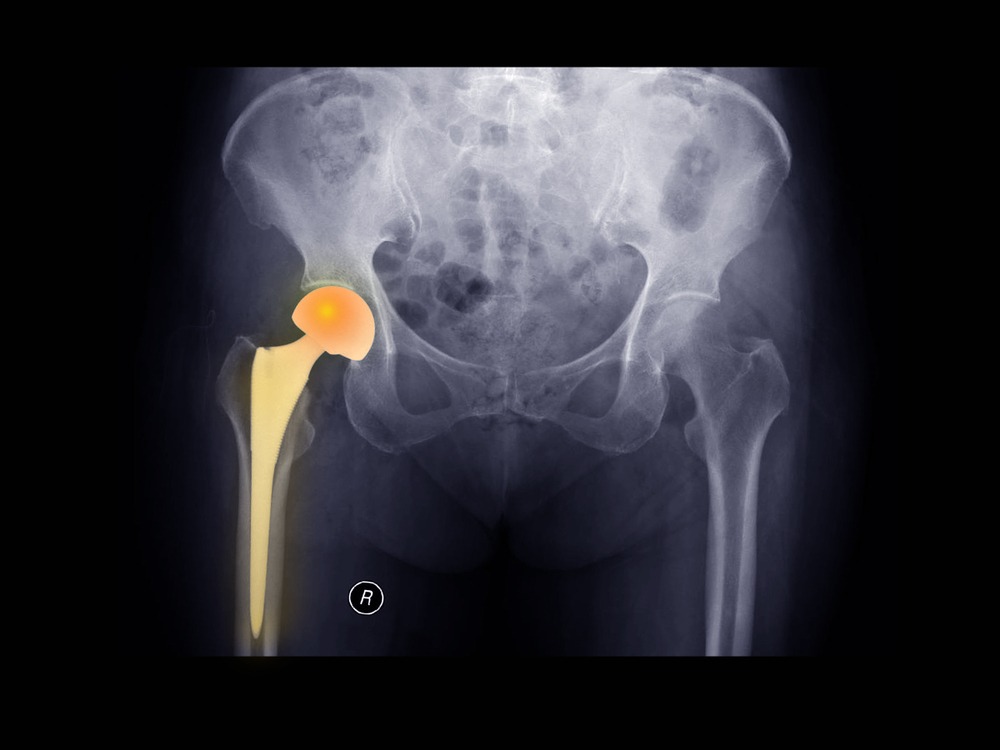

Η ολική αρθροπλαστική ισχίου αποτελεί την οριστική λύση για τελικού σταδίου αρθρίτιδες του ισχίου. Η επέμβαση θεωρείται από τις πιο επιτυχημένες στην Ιατρική, καθώς επιφέρει πολύ καλά έως εξαιρετικά αποτελέσματα στους περισσότερους ασθενείς. Μάλιστα, αυτό επιβεβαιώνεται από τη διεθνή βιβλιογραφία και τις βάσεις δεδομένων αρθροπλαστικών (registries) του εξωτερικού.

Φυσικά, ο χειρουργός διαθέτει κάποια μέσα ώστε να προφυλάξει τους ασθενείς από αυτά τα δύο σοβαρά προβλήματα. Ένα από αυτά είναι η χρήση προηγμένης τεχνολογίας για την υποβοήθηση κατά την τοποθέτηση των εμφυτευμάτων.

- Εξατομικευμένος σχεδιασμός τοποθέτησης των εμφυτευμάτων και ζωντανή συσχέτιση με το διεγχειρητικό αποτέλεσμα, καθώς και χρήση του σωστού εμφυτεύματος για τον εκάστοτε ασθενή (personalized cup position)